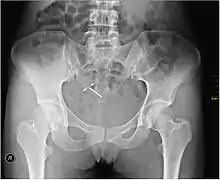

An intrauterine device (IUD), also known as intrauterine contraceptive device (IUCD or ICD) or coil, is a small, often T-shaped birth control device that is inserted into the uterus to prevent pregnancy.

- Because the first intrauterine contraceptive device proposed by Dr Richard Richter in 1909 was ignored, the Silver Ring of Dr Ernst Gräfenberg (1928) is currently labeled as the prototype of modern IUD generations. The Ring of Gräfenberg, however, was proscribed in the 1930s, and, although the basis for the condemnation was more political than scientific, three decades had passed before the rebirth and general acceptance of intrauterine contraception. The development of the plastic IUDs, announced by Dr Lazar Margulies and Dr Jack Lippes in 1960-61, solved the insertion problem of metallic IUDs, but did not eliminate the main side-effects, that is, bleeding and pain. In 1969, the first copper-bearing device was introduced by Dr Jaime Zipper and Dr Howard Tatum. The metallic contraceptive adjuvant, though allowing reduction of the platform size, did not solve the menorrhagia problem. This was achieved by Dr Tapani Luukkainen thanks to the invention of the gestagen- releasing IUD (Ng Nova-T) in 1977. The final step in IUD engineering was the invention of the GyneFix, a flexible, frameless copper-bearing IUD anchored permanently to the uterine tissues, which the inventor (Dr Dirk Wildemeersch) calls an intrauterine contraceptive implant or IUCI.